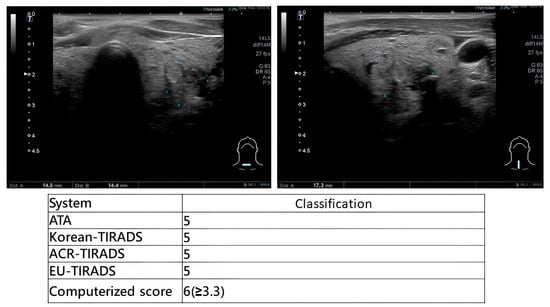

Comparative Diagnostic Performance of Ultrasound-Based Risk Stratification Systems in Thyroid Nodule Evaluations by Otolaryngologists

Background/Objectives: Thyroid nodules are a prevalent condition with a high incidence rate of malignancy. Ultrasound (US)-based risk stratification systems have become widely utilized for the evaluation of thyroid nodules, including the American Thyroid Association (ATA) guidelines, the American College of Radiology Thyroid Imaging [...] Read more.

Background/Objectives: Thyroid nodules are a prevalent condition with a high incidence rate of malignancy. Ultrasound (US)-based risk stratification systems have become widely utilized for the evaluation of thyroid nodules, including the American Thyroid Association (ATA) guidelines, the American College of Radiology Thyroid Imaging Reporting and Data System (ACR-TIRADS), the Korean Society of Thyroid Radiology system (K-TIRADS), and the European Thyroid Association system (EU-TIRADS). Our institution has developed a real-time computerized score for evaluating thyroid nodules. This study aims to systematically compare the diagnostic performance of these systems when applied in real time by otolaryngologists, who integrate dynamic US imaging with physical examination. Methods: Patients with thyroid nodules who underwent US evaluation, US-guided fine-needle aspiration cytology (FNAC), and subsequent thyroidectomy were included. During each examination, otolaryngologists performed real-time risk categorization according to five US-based systems, with immediate scoring based on dynamic sonographic findings. Results: From April 2021 to November 2023, 130 patients were enrolled. For categories 4 and 5, the ATA guidelines had a sensitivity of 96.6% (95% CI: 87.3–100%), specificity of 78.9%, (60.6–97.3%) PPV of 84.6% (70.7–98.5%), NPV of 93.7% (81.9–100%), and accuracy of 88.1% (78.3–97.9%). The sensitivity of the ACR-TIRADS was 95.6% (87.3–100%), the specificity was 78.9% (60.6–97.3%), the PPV was 84.6% (70.7–98.5%), the NPV was 93.7% (81.9–100%), and the accuracy was 88.1% (78.3–97.9%). Both the K-TIRADS and the EU-TIRADS had sensitivities of 95.6% (87.3–100%), specificities of 78.9% (60.6–97.3%), PPVs of 84.6% (70.7–98.5%), NPVs of 93.7% (81.9–100%), and accuracies of 88.1% (78.3–97.9%). The computerized score (>3.3 considered malignant) and TBSRTC (Category 5 or 6) both had sensitivities of 73.9% (56.0–91.9%), specificities of 100%, PPVs of 100%, NPVs of 76.0% (59.3–92.7%), and accuracies of 85.7% (75.1–96.3%). Conclusions: Otolaryngologists can achieve highly accurate diagnostic performance when applying standardized ultrasound-based risk stratification systems, and a real-time computerized scoring system provides highly specific supplemental value for immediate clinical decision-making. Full article

Show Figures

Figure 1